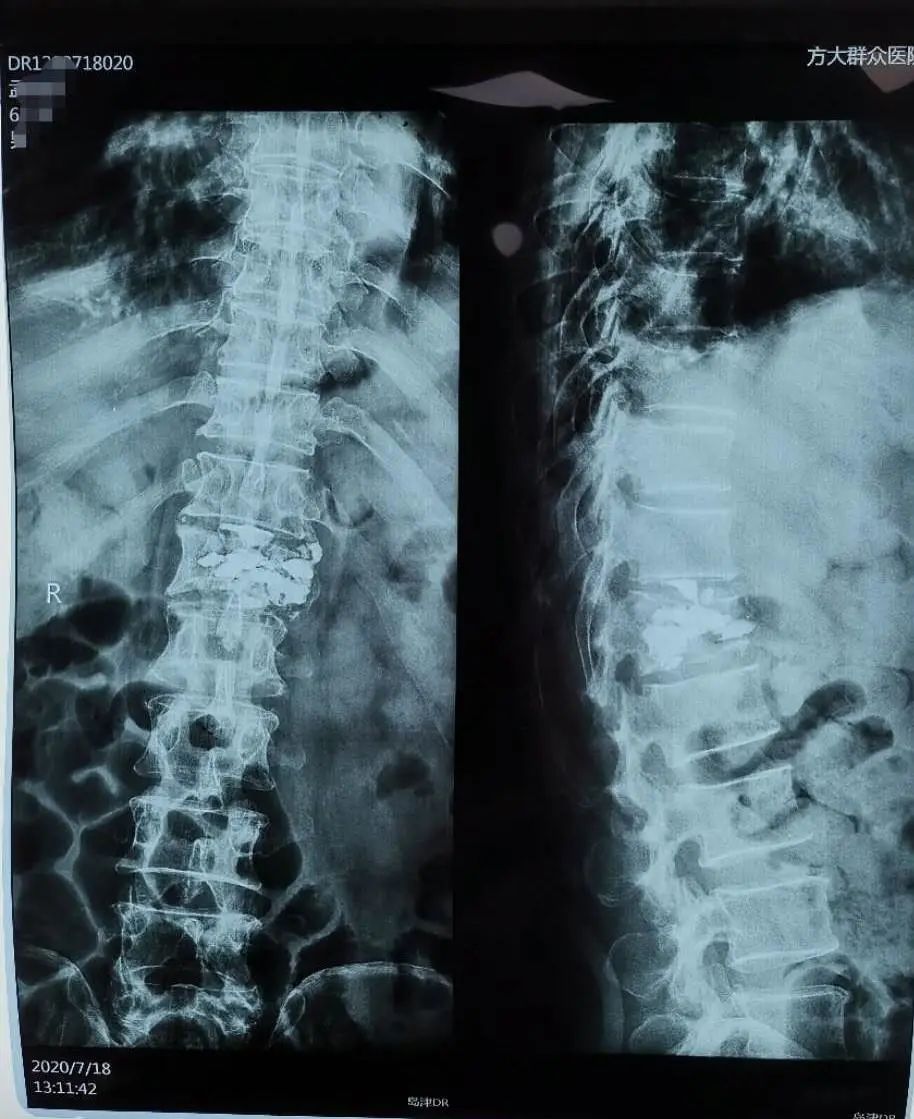

我院骨二科最新开展椎体成型术,成功为一位因癌转移造成十二胸椎压缩性骨折患者实施了椎体成形微创手术,取得良好效果。

65岁的孟先生,身患6种癌症,带癌生存10年,先后做过大小17次手术。他乐观向上,顽强地与病魔抗争。可上天似乎又和他开了一个玩笑,一个月前他胸背部疼痛,夜间尤甚,彻夜难眠,经相关检查诊断为:癌转移造成十二胸椎压缩性骨折。为了减轻痛苦,孝顺的儿女慕名找到骨二科赵胜主任,并且只有一个要求,只要能减轻父亲的疼痛就行,不奢求下地行走。赵主任、金殿鑫副主任立即请中国医科大学附属一院骨科脊柱专家远程会诊,结合患者的身体状况,最终决定采用椎体成形术进行微创治疗。在中国医科大学附属一院骨科脊柱专家指导下,手术取得圆满成功。术后患者疼痛明显减轻,一周后下床行走,避免了开放手术带来的创伤大及卧床时间长等弊端。看着下地行走的孟先生,家属不相信地瞪大了双眼,连连表示感谢,为方大群众医院和骨二科竖起了大拇指。